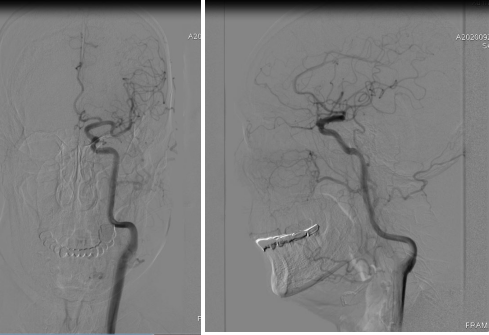

外院DSA

右颈动脉

左椎动脉

左颈动脉

诊断:右侧前交通动脉瘤

患者在全麻下、多参数监护仪监测下行前交通动脉瘤经右侧颈内动脉支架辅助下栓塞术。全麻后,常规消毒销巾,采用改良seldinger技术穿刺右侧股动脉或功,置入6F动脉鞘。黑泥鳅导丝及多功能导管带领6F MPD导管达到右侧颈内动脉岩段,行造影见∶前交通动脉瘤,瘤体3.5 mm*5.1 mm。在路图引导下,徵导丝(Synchro 0.014 in*200 cm)带领弹支架微导管(SL-10)到右侧大脑前动脉A2段,退出微导丝。微导丝(Synchro 0.014 in*200 cm)带领弹簧圈微导管(eV3 Echelon-10)到达前交通动脉瘤体内,退出微导丝。经弹簧圈微导管填入首枚弹簧圈(Codman COMPLEX XTRASOFT3 mm*6 cm)成篮良好,在路图引导下在支架管内输送支架(Neuroform Atlas 3.0 mm*21 mm)并释放完全覆盖动脉瘤颈,造影可见支架打开良好解脱首枚弹备圈,沿弹簧圈导管继续填入弹簧圈(可见护理记录单)间断造影确保双侧大脑前动脉血流通畅。右侧颈内动脉造影确认∶前交通动脉瘤填塞致密,双侧大应前动脉血流通畅。手术结束。右侧股动脉鞘处用血管封堵器(Coxrds Exoseal 6F)封堵,并压迫器持续压迫。木后患者清醒。